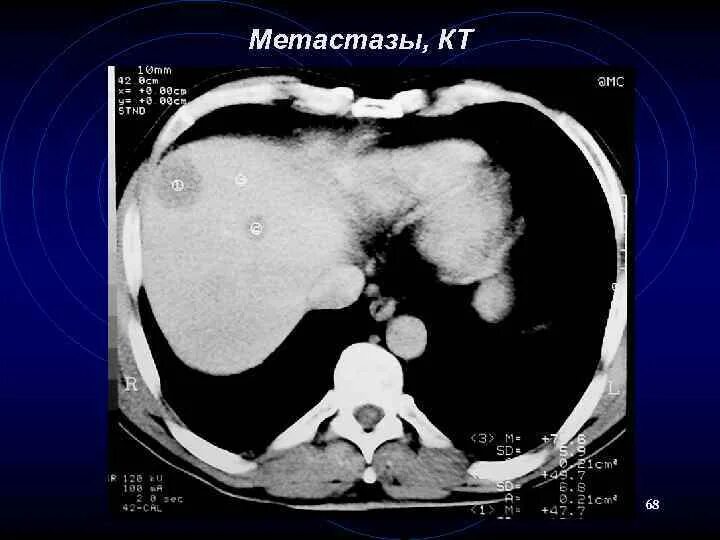

Метастазы в печени на узи прогноз